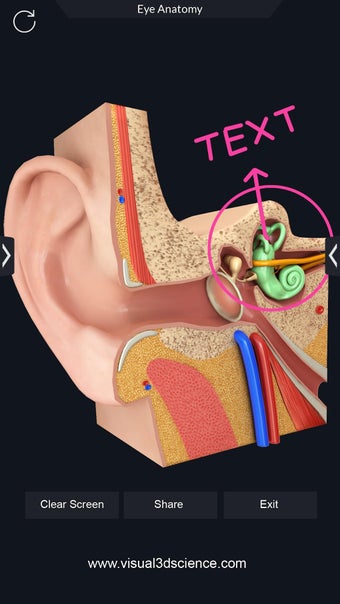

Met deze applicatie kun je 360° draaien rond een zeer realistisch 3D-model van het menselijk lichaam. Je kunt in- en uitzoomen op elk deel om er beter naar te kijken.

De camera kan worden verplaatst om een ander beeld van elk deel te krijgen.

Je kunt alle informatie over de organen krijgen, inclusief hun locatie, hun functie en hoe ze eruitzien.